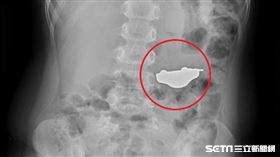

5歲童誤吞玩具 照X光…肚裡一輛車

真的是嚇壞家長!台中一名5歲大男童小傑(化名)一日躺...